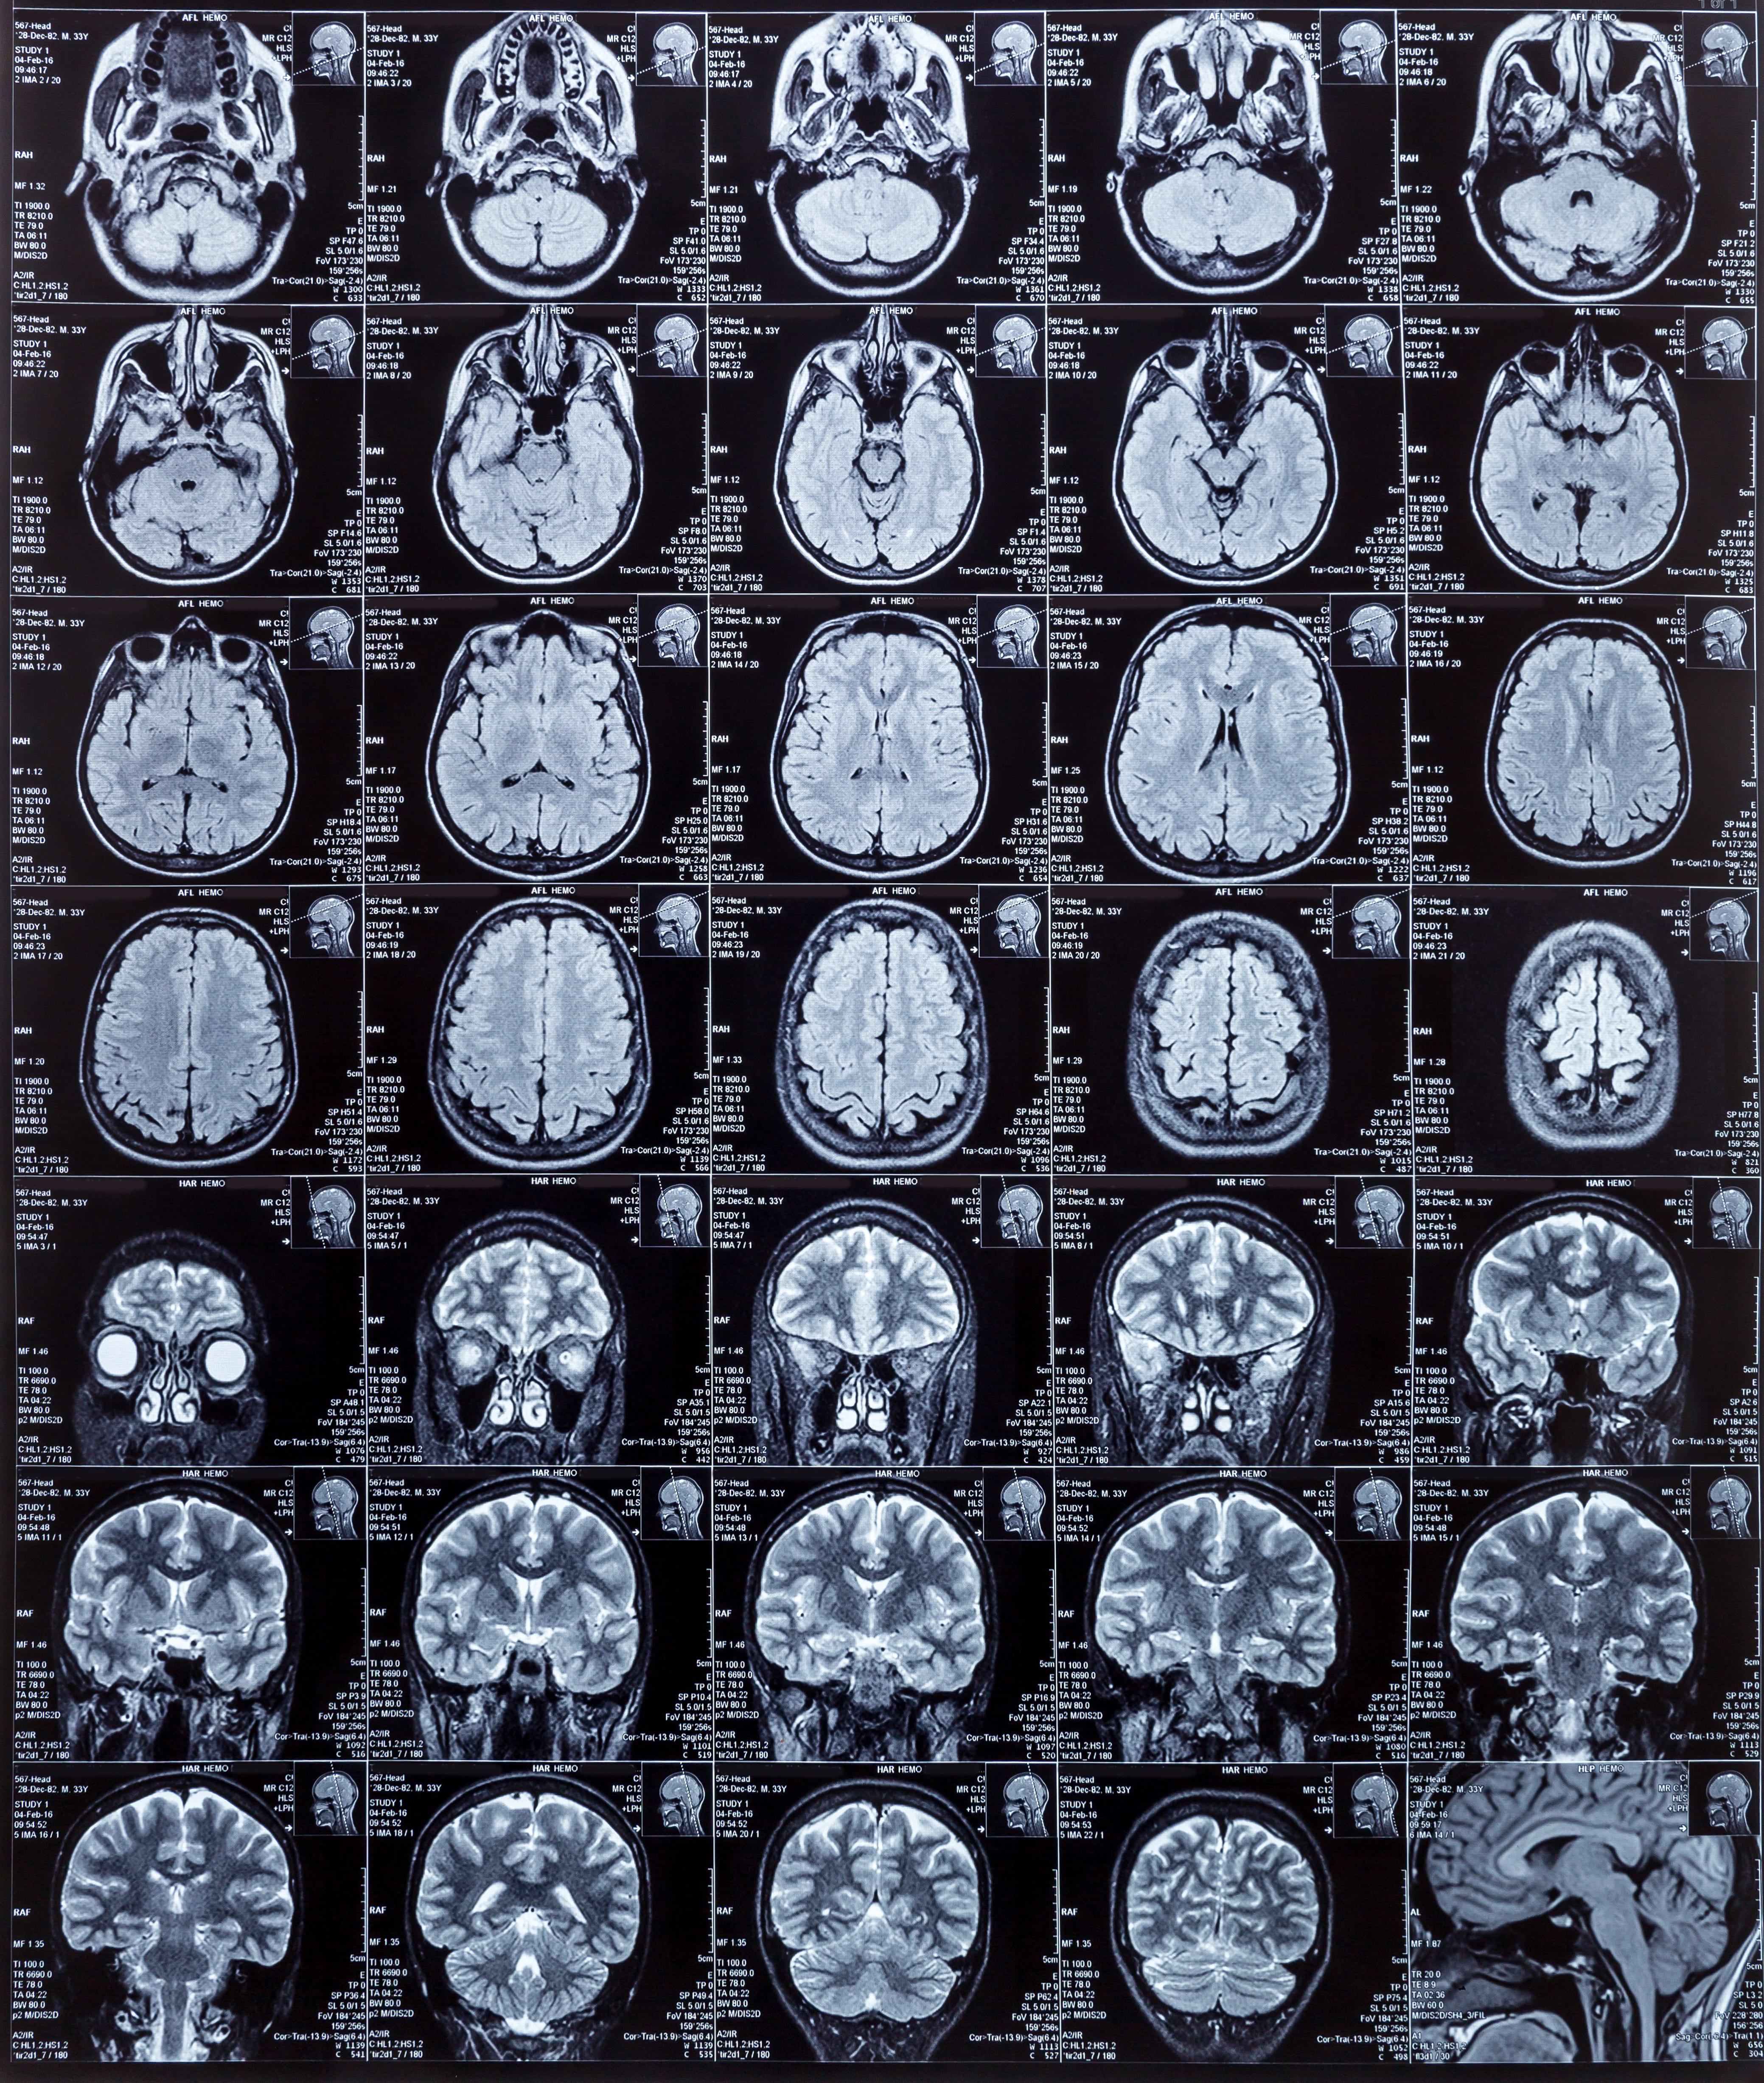

L'IRM cérébrale visualise le cervelet et détecte d'éventuelles lésions ou une atrophie cérébelleuse caractéristique des formes dégénératives. Les analyses sanguines recherchent des causes curables : carences vitaminiques, troubles thyroïdiens, maladies auto-immunes. Les tests génétiques identifient les mutations spécifiques dans les formes héréditaires autosomiques dominantes ou récessives.